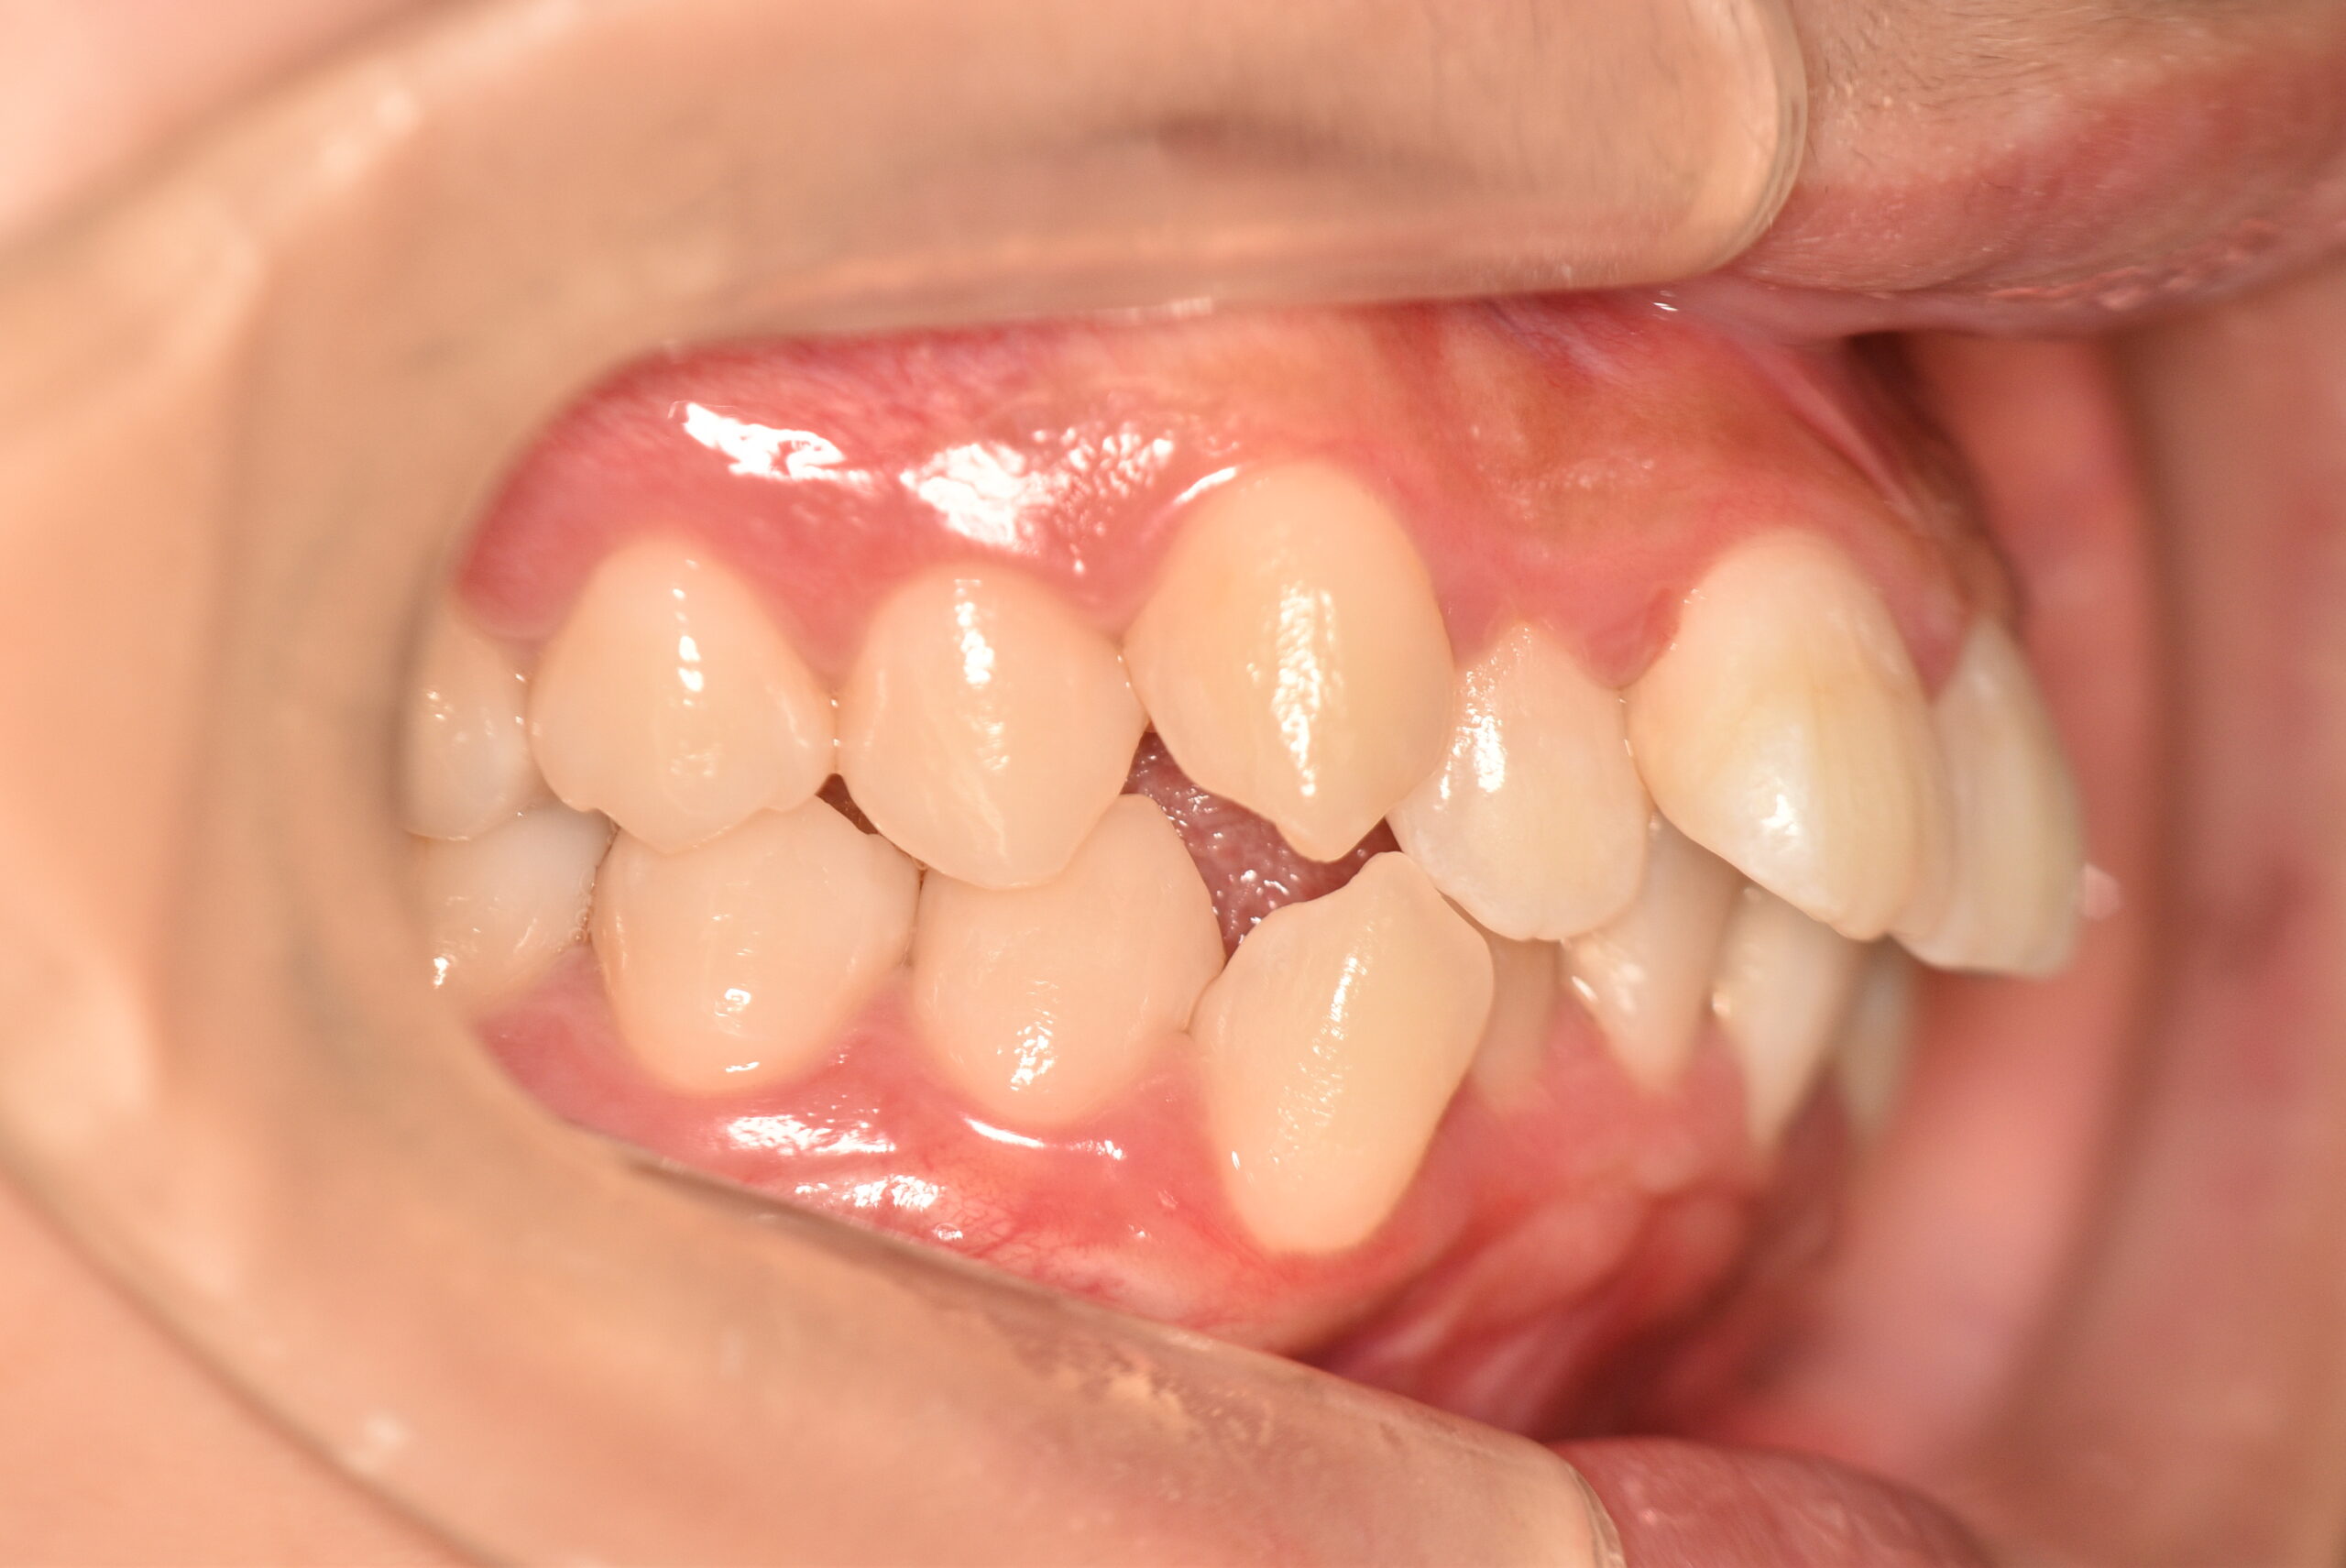

でっ歯(抜歯)【2247】

初診時

20歳 性 別 女性

治療期間 2年1ヶ月 費 用 矯正施術料:1,000,000円

治療内容の詳細 初診時20歳の女性で、出っ歯、歯のがたつきを気にされ来院しました。

検査の結果、上下顎前歯部叢生を伴うアングルⅠ級不正咬合と診断しました。

治療としては、上下左右第一小臼歯を抜歯の上、セルフライゲーションブラケット装置(デーモンシステム)と

マウスピース矯正装置(インビザライン)で配列を行いました。

この際、上顎に歯科矯正用アンカースクリューを設置し上顎前歯部後退時の土台としました。

治療期間は2年1ヶ月でした。